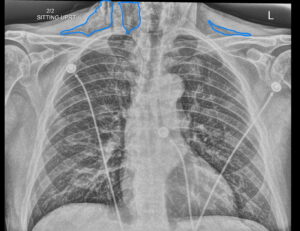

Dental Free Air CXR 2 Inverted Annotated. JETem 2025